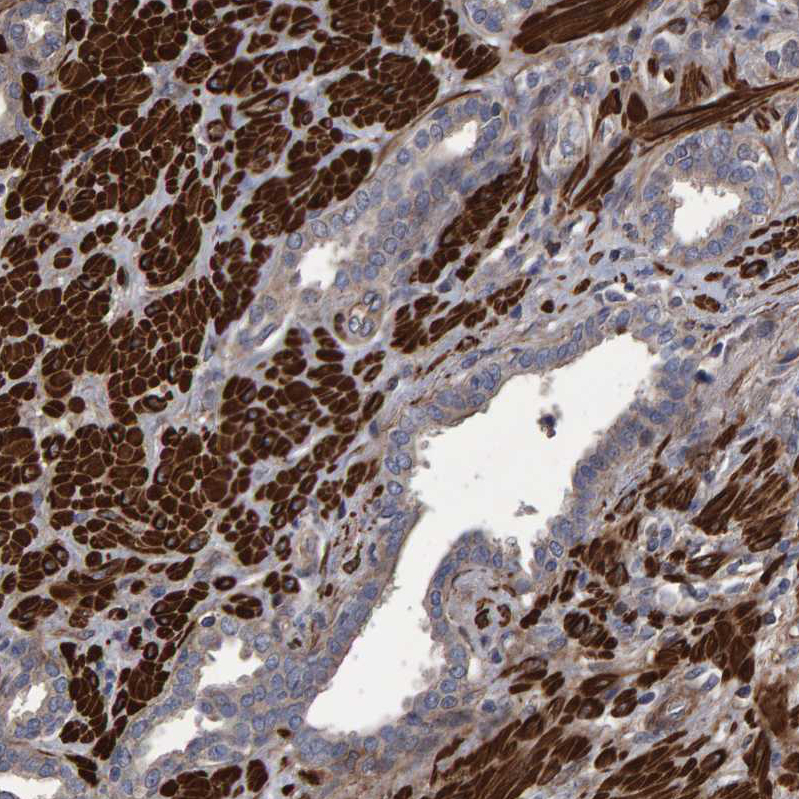

Immunohistochemical staining of human lung shows strong cytoplasmic positivity in macrophages.